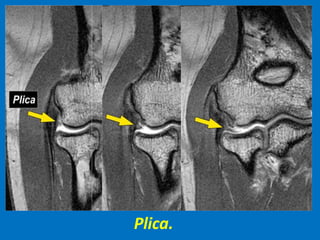

Plica.